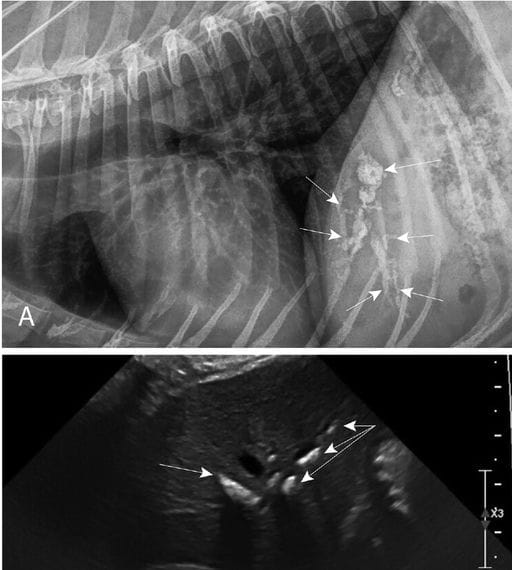

Radiographic and ultrasound images of a dog with identified hepatoliths that underwent a cholecystectomy between January 2014 to May 2024. A—A right lateral radiograph showing moderate hepatoliths (arrows). B—An ultrasound image of the same dog with the mineralizations visualized as linear hyperechoic regions (arrows) within the liver that cast an acoustic shadow.